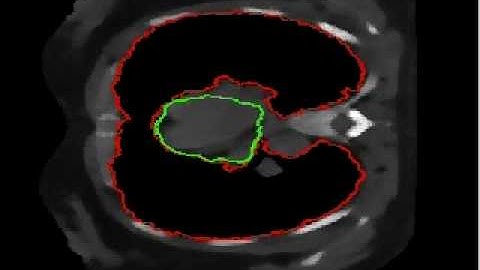

4D heart segmentation from CTA by atlas segmentation and 4D registration